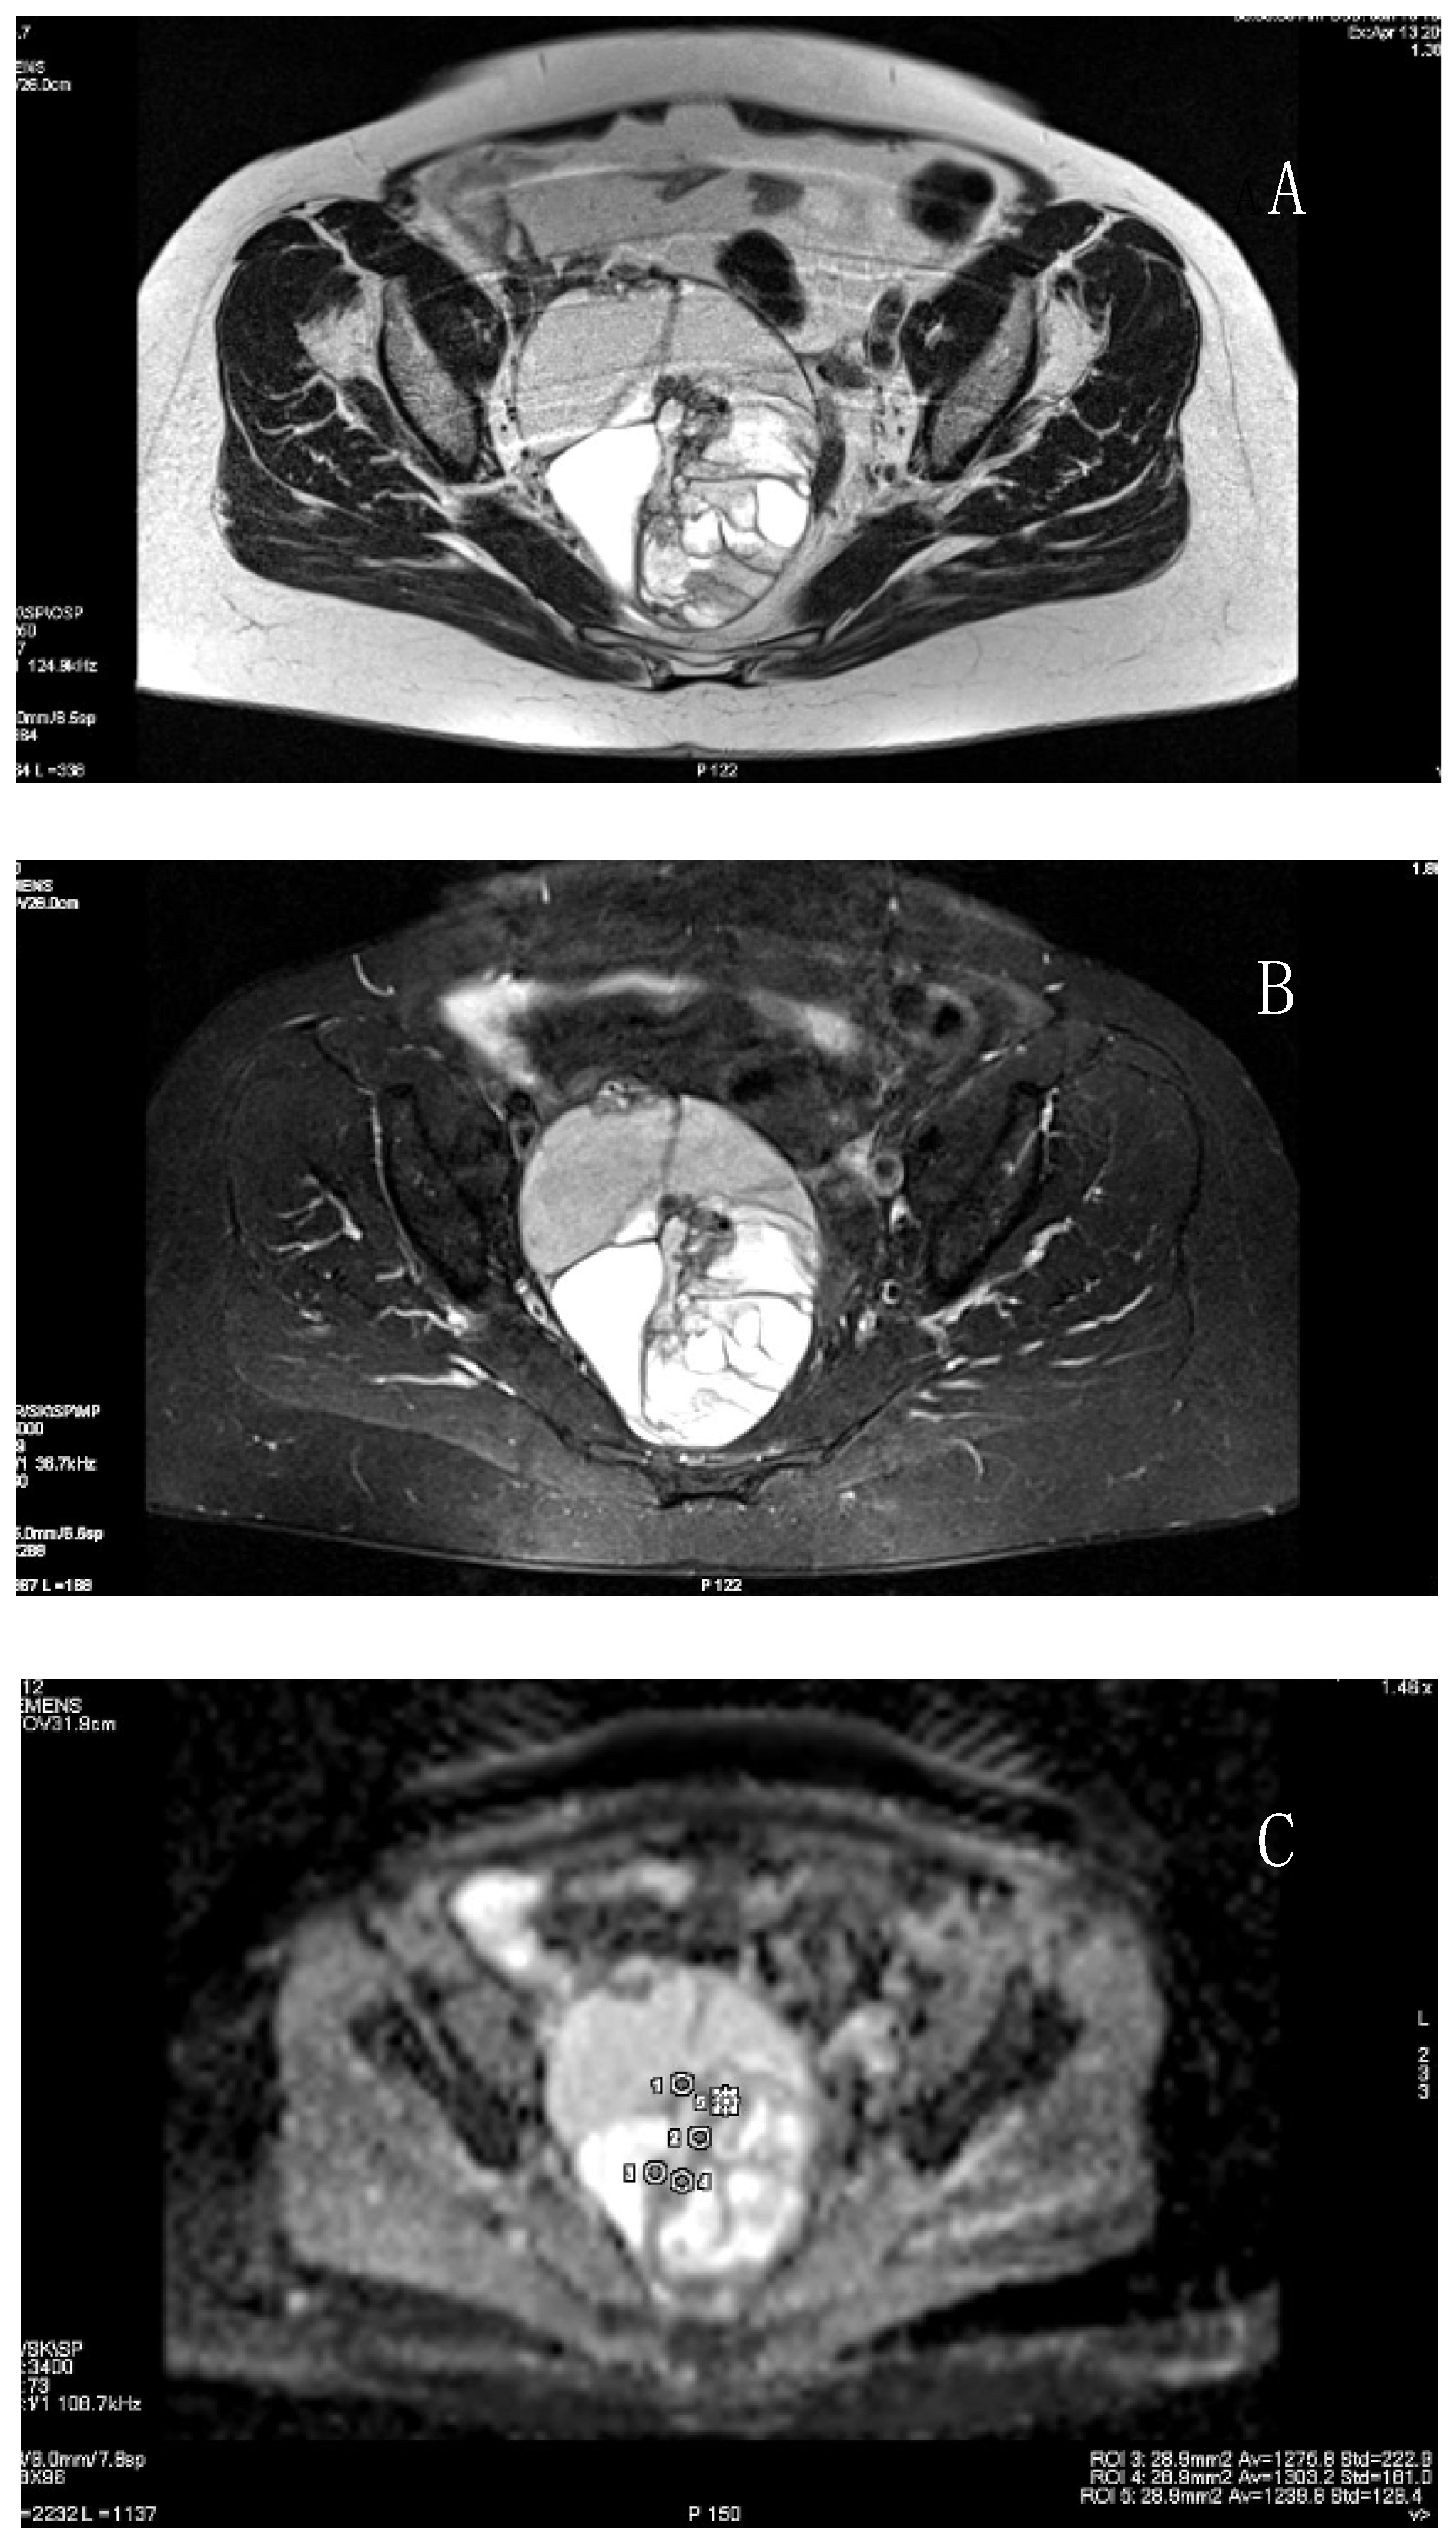

3.1. Primary Tumor

3.2. MRI DWI and DCE Parameters and Immunohistochemistry